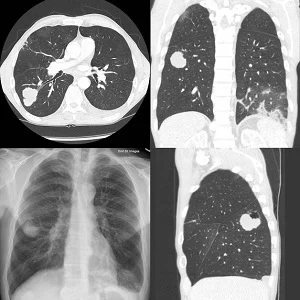

Researchers at Brigham and Women’s Hospital (Boston, MA) recently published a study in the Journal of the American College of Radiology showing that patient retention in a lung cancer screening (LCS) programme drops after diagnostic chest computed tomography (CT) examinations.

Lung cancer is the leading cause of US cancer-related death, and screening with low radiation dose CT can reduce the disease mortality. Patients in LCS programmes with low-dose CTs may receive diagnostic chest CTs to follow up nodules. Since diagnostic CTs come with higher radiation exposures, this can lead to patient loss from LCS programmes.

Of the 5,912 patients who underwent LCS CT between June 2011 and August 2018, only 2,756 (46.6%) received subsequent diagnostic CTs in the screening programme. Only 1,240 (20.9%) patients experienced at least three chest CT examinations in the study period. Of 711 patients whose subsequent CT study was LCS CT, 585 (82%) underwent the following LCS CT. In comparison, of 529 patients who underwent subsequent diagnostic CT, only 208 (39%) undertook the LCS CT.